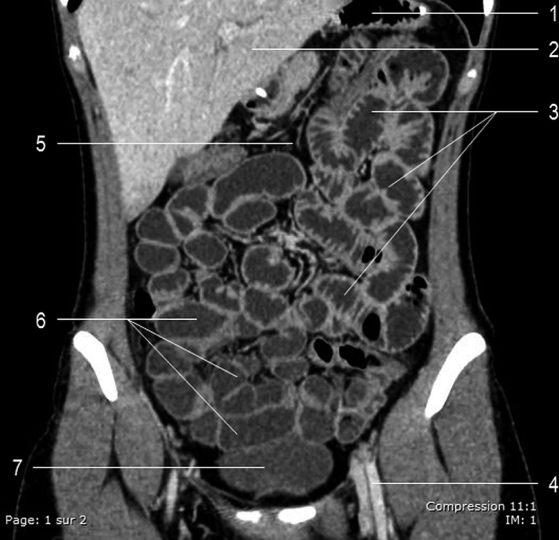

Fig. 2.6 Reconstruction coronale d’une séquence d’entéroscanner après ingestion de 1,5 litre de liquide par la bouche et injection intraveineuse de produit de contraste iodé.

1. Estomac. 2. Foie. 3. Jéjunum. 4. Vaisseaux fémoraux gauches. 5. Mésentère. 6. Iléon. 7. Vessie.